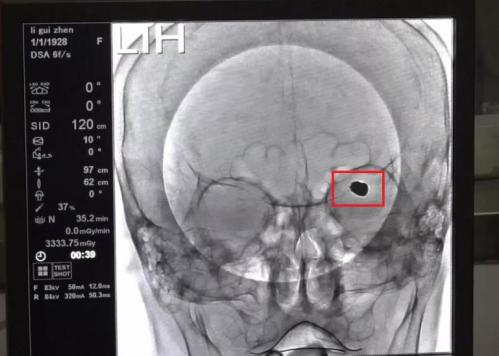

(术后填充的动脉瘤)

据李宏宇主任介绍,李阿姨脑动脉瘤大小8mmX6mm,在他多年临床工作中也属罕见。在术前准备后中午12时30分手术正式开始,通俗讲动脉瘤介入栓塞治疗就是将介入导丝填充进血管瘤内,让血液不再经过血管瘤,从而让这个大脑内部的“*弹炸**”不会因血压“引爆”。在李宏宇手术团队的配合下,介入导丝从患者的腿部动脉一点一点推入到患者脑内的血管瘤病灶处,紧接着在血管瘤内填入导丝封住血管瘤。经过2个多小时紧张工作,手术顺利完成。

笔者采访到李宏宇主任,他表示,此次手术的风险性和难度比较大。风险主要是患者超过90岁,各脏器功能都不理想,我们要考虑全麻手术状态下,患者心肺、肾功能是否跟得上。同时,患者脑血管基础不好,右侧颈动脉已经闭塞,仅靠左侧颈动脉供应全脑血流。所以,一旦有个闪失,可能会导致周边大面积的血栓,出现生命危险。患者脑部动脉瘤瘤体过大,达到8mmX6mm。我们说5mm是动脉瘤最大观察范围,它已经超过最大观察范围,随时可能会爆裂,导致患者脑内大量出血死亡。手术难度主要是此动脉瘤形态和大脑中动脉的一支血管关系十分密切,我们用一个支架导管保护一条主杆血管,必须在完美填塞大动脉瘤的前提下,保护好周边两根重要血管。如果那两只血管有一根损伤,病人可能会出现一侧肢体残疾或不会说话,导致将来出现后遗症。但是,我们在整个手术过程中完美地保留了血管,成功地完成了此次动脉瘤介入栓塞日间手术。